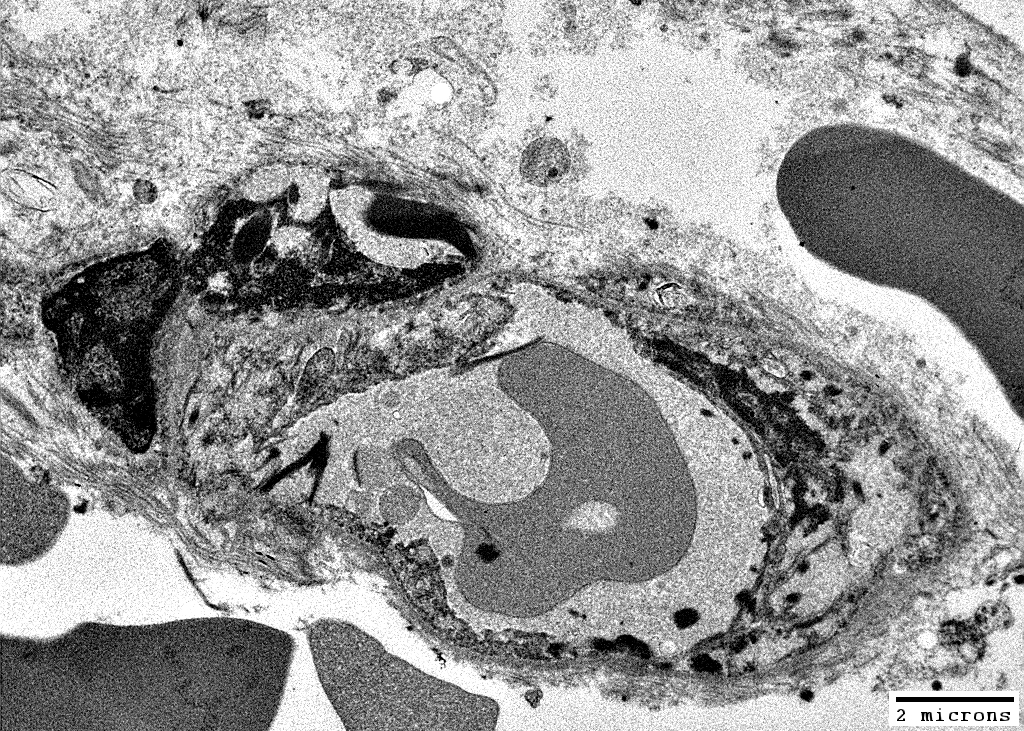

MELAS: Mitochondrial Ultrastructure

From: R Schmidt

Pericytes   Mitochondrial proliferation & enlargement (Black arrows)

Endothelial cells   Multiple small vacuoles (White arrows)

Large cells near vessels with

Mitochondrial proliferation & enlargement

Lipid droplets